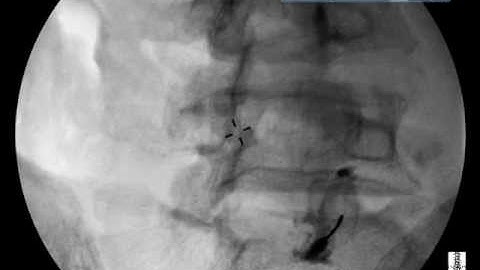

Before Facet Injection Do This! | Lumbar Facet Injection